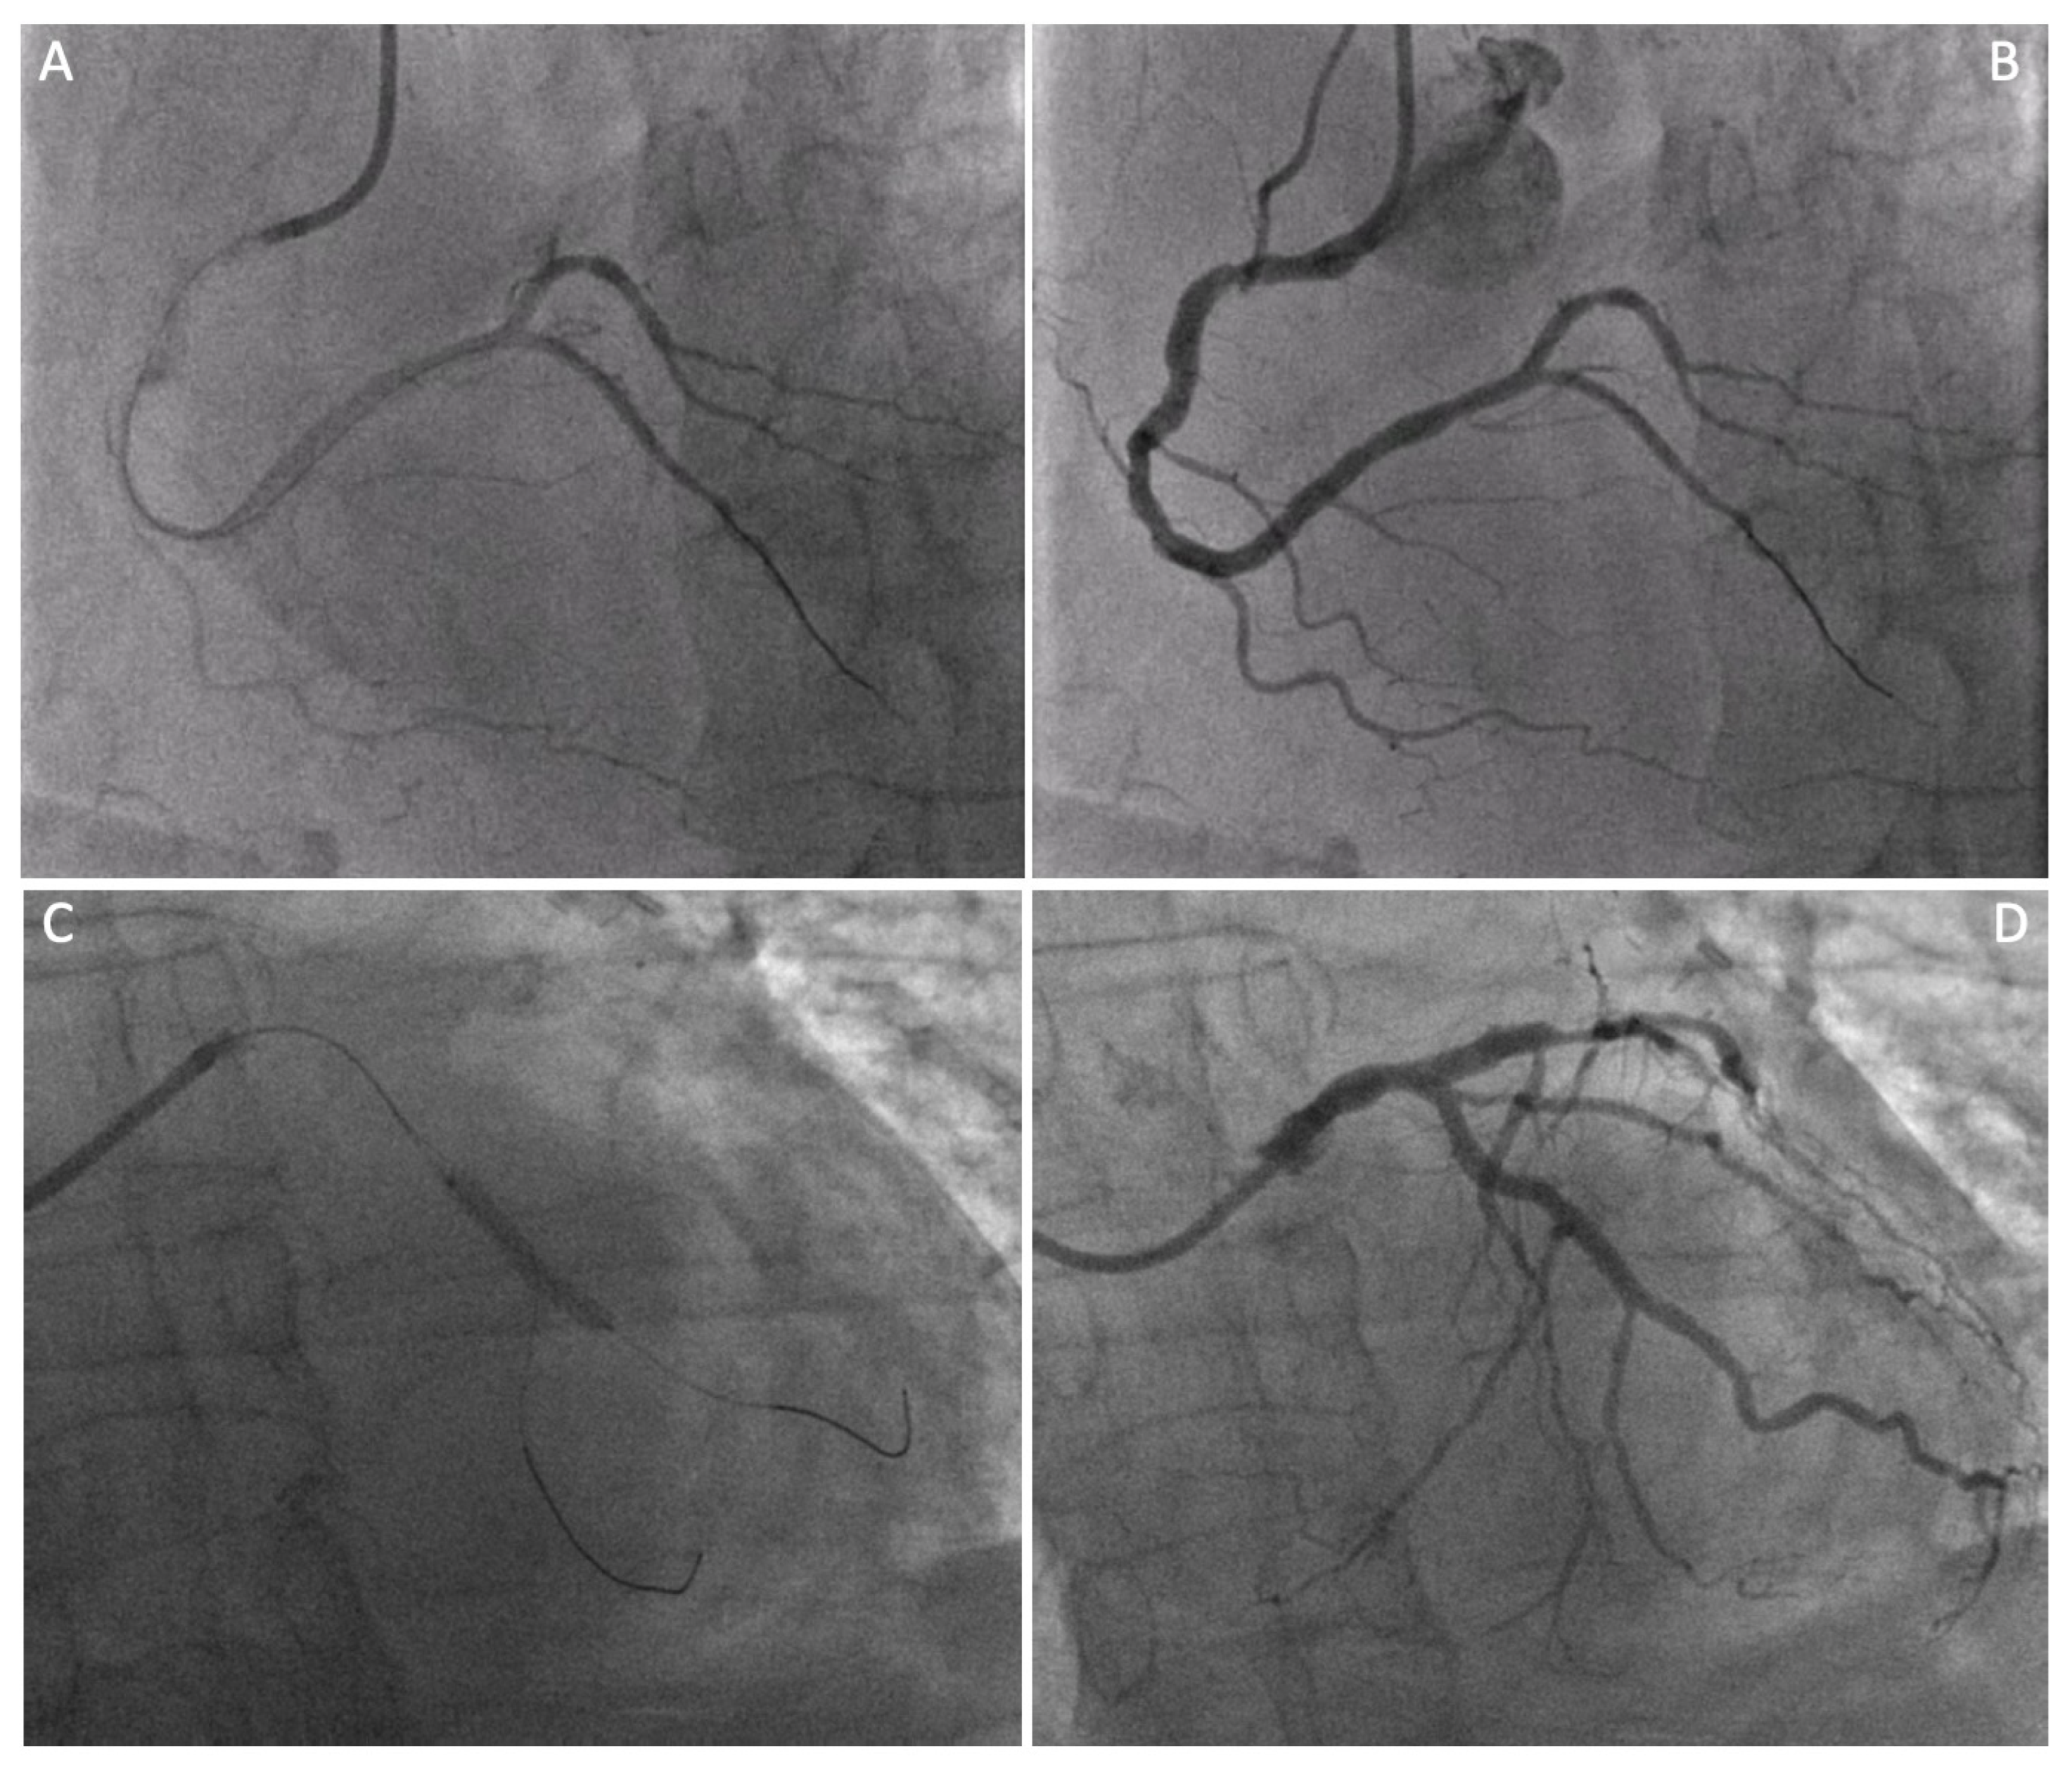

| Graft failure | 2 (2.1) | 0 (0%) |

| Sternotomy conversion | 2 (2.1) | 0 (0%) |

| LIMA angiographic patency at staged PCI (n° of pts, %) | 10 (100%) |